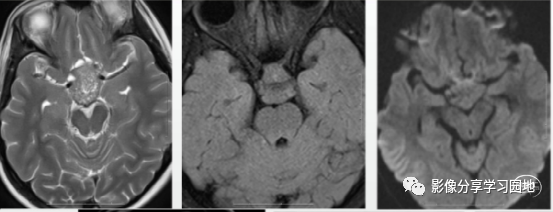

病例4 右侧基底节区生殖细胞瘤。MRI图像T2WI呈稍高信号(A),DWI 呈高信号(B),增强后斑片状明显强化(C),右侧基底节丘脑、 右侧大脑半球及右侧大脑脚萎缩(A、D),提示华勒氏变性。

病例5 男,8岁,右侧基底节区生殖细胞瘤,A、B图像MRIT1WI、T2WI肿瘤实质呈等信号,其内可见长T1长T2信号,轻度占位效应,无水肿,肿瘤沿前联合浸润至对侧基底节区,呈等信号,C、右侧大脑脚萎缩(长箭)。D、CT平扫呈明显高密度影,其内可见囊性变,左侧基底节区可见病变浸润呈高密度影(短箭头)。

病例6 男,12岁,左侧基底节区生殖细胞瘤,A、DWI呈高信号,B、CT呈高密度影C、MRIT1增强呈结节样明显强化,D、T2WI左侧大脑脚萎缩(长箭头)。